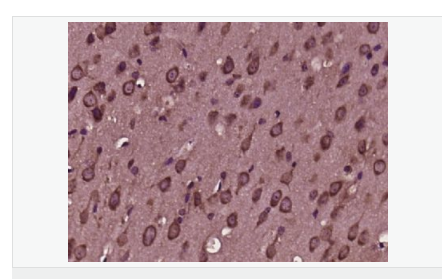

| 產(chǎn)品應(yīng)用 | ELISA=1:5000-10000 IHC-P=1:100-500 IHC-F=1:100-500 IF=1:100-500 (石蠟切片需做抗原修復(fù)) not yet tested in other applications. optimal dilutions/concentrations should be determined by the end user. |

| 免 疫 原 | KLH conjugated synthetic peptide derived from human SQSTM1/p62:51-150/440 |

| 產(chǎn)品介紹 | Adapter protein which binds ubiquitin and may regulate the activation of NFKB1 by TNF-alpha, nerve growth factor (NGF) and interleukin-1. May play a role in titin/TTN downstream signaling in muscle cells. May regulate signaling cascades through ubiquitination. Adapter that mediates the interaction between TRAF6 and CYLD (By similarity). May be involved in cell differentiation, apoptosis, immune response and regulation of K(+) channels. Function: Adapter protein which binds ubiquitin and may regulate the activation of NFKB1 by TNF-alpha, nerve growth factor (NGF) and interleukin-1. May play a role in titin/TTN downstream signaling in muscle cells. May regulate signaling cascades through ubiquitination. Adapter that mediates the interaction between TRAF6 and CYLD (By similarity). May be involved in cell differentiation, apoptosis, immune response and regulation of K(+) channels. Subunit: Cytoplasm. Late endosome. Nucleus. Endoplasmic reticulum. Note=Sarcomere. In cardiac muscles localizes to the sarcomeric band. Localizes to late endosomes. May also localize to the nucleus. Accumulates in neurofibrillary tangles and in Lewy bodies of neurons from individuals with Alzheimer and Parkinson disease respectively. Enriched in Rosenthal fibers of pilocytic astrocytoma. In liver cells, accumulates in Mallory bodies associated with alcoholic hepatitis, Wilson disease, indian childhood cirrhosis and in hyaline bodies associated with hepatocellular carcinoma. Colocalizes with TRIM13 in the perinuclear endoplasmic reticulum. Subcellular Location: Cytoplasm. Late endosome. Nucleus. Sarcomere (By similarity). In cardiac muscles localizes to the sarcomeric band (By similarity). Localizes to late endosomes. May also localize to the nucleus. Accumulates in neurofibrillary tangles and in Lewy bodies of neurons from individuals with Alzheimer and Parkinson disease respectively. Enriched in Rosenthal fibers of pilocytic astrocytoma. In liver cells, accumulates in Mallory bodies associated with alcoholic hepatitis, Wilson disease, indian childhood cirrhosis and in hyaline bodies associated with hepatocellular carcinoma. Tissue Specificity: Ubiquitously expressed. Post-translational modifications: Phosphorylated. May be phosphorylated by PRKCZ (By similarity). Phosphorylated in vitro by TTN. DISEASE: Defects in SQSTM1 are a cause of Paget disease of bone (PDB) [MIM:602080]. PDB is a metabolic bone disease affecting the axial skeleton and characterized by focal areas of increased and disorganized bone turn-over due to activated osteoclasts. Manifestations of the disease include bone pain, deformity, pathological fractures, deafness, neurological complications and increased risk of osteosarcoma. PDB is a chronic disease affecting 2 to 3% of the population above the age of 40 years. Similarity: Contains 1 OPR domain. Contains 1 UBA domain. Contains 1 ZZ-type zinc finger. SWISS: Q13501 Gene ID: 8878 Database links: Entrez Gene: 8878 Human Entrez Gene: 18412 Mouse Omim: 601530 Human SwissProt: Q13501 Human SwissProt: Q64337 Mouse Unigene: 709030 Human Unigene: 40828 Mouse Unigene: 107103 Rat Important Note: This product as supplied is intended for research use only, not for use in human, therapeutic or diagnostic applications. |